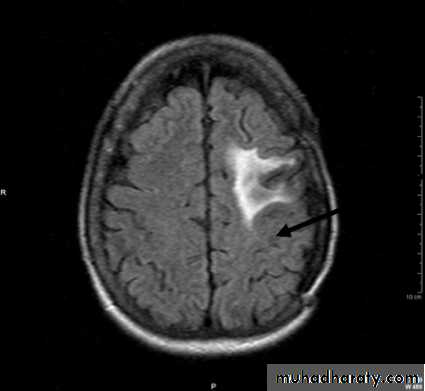

• Computed Tomography scan (CT scan) with/without contrast• Magnetic Resonance Imaging (MRI) with/without contrast